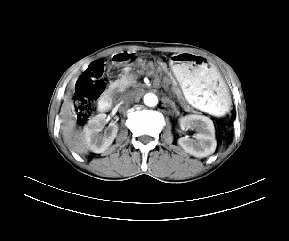

标题: CT19533:病变来源于哪?

患者,男,发现上腹部包块两月余。

病变位于肝胃间隙,实际就是位于小网膜囊(左肝下后间隙),呈轻度不均匀性强化,腹腔内及腹膜后见多发肿大淋巴结。所以我考虑肝胃间隙恶性胃肠间质瘤并淋巴结转移。

病灶强化不显著,灶周及腹膜后见多量淋巴结肿大,考虑淋巴瘤可能,其次考虑间质瘤

病灶与胰腺分界不清,来源于胰腺?

强化后病变与胃壁分界清楚,并且血供不是来源胃壁血管。考虑胰腺颈体癌并腹腔腹膜后淋巴结转移。